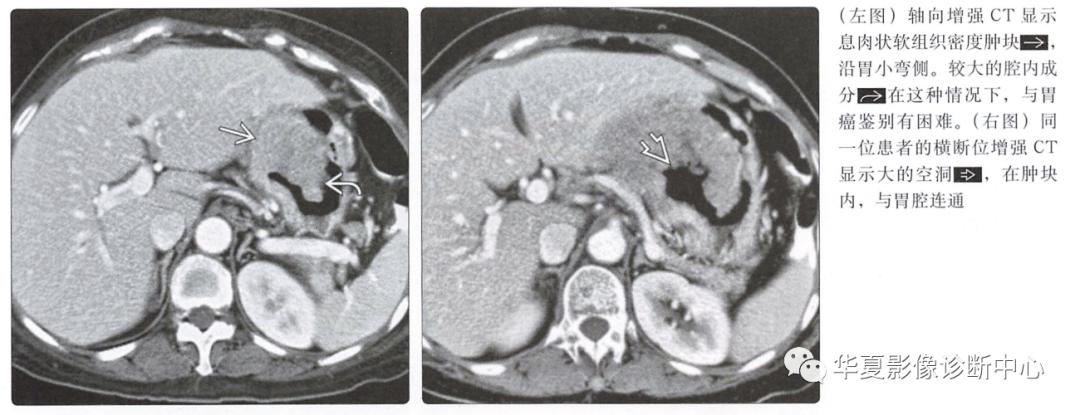

增强CT

动脉期图像呈低或高血供,边界清楚的黏膜下肿块;溃疡和坏死是常见的

具有大的腔内成分的肿瘤可能类似原发性胃癌

外生性胃癌

低密度肿块, 血管少于GIST

CT或MR可能体积庞大且外生

邻近胃壁的局灶性增厚和胃出口阻塞可以帮助区分GIST